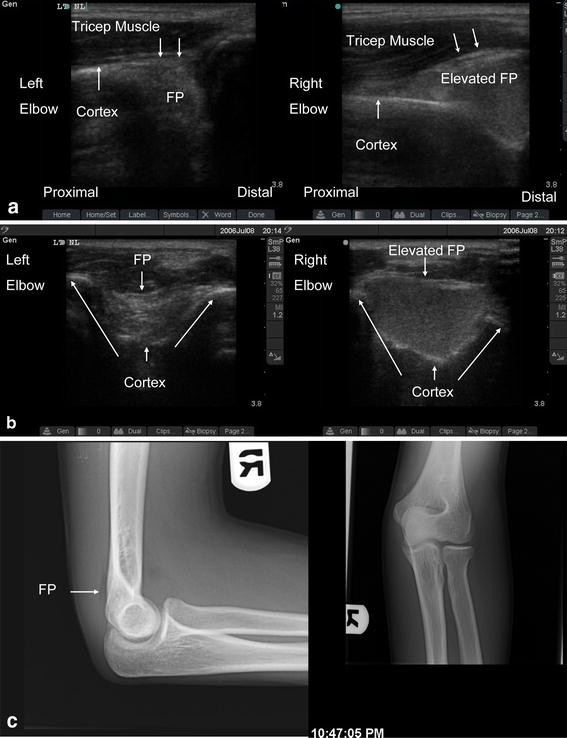

Sonographic fat pad sign. A teenage boy injured his elbow after a fall

Sonographic fat pad sign. A teenage boy injured his elbow after a fall Fat Pad Sign Elbow Injury  It means there is swelling in the. This could be due to swelling in that area of the elbow.  although fat pad signs are classically associated with fracture, there are many nontraumatic disease processes which.  the posterior fat pad sign is the visualization of a lucent crescent of fat located in the olecranon fossa on a true lateral. Fat Pad Sign Elbow Injury.